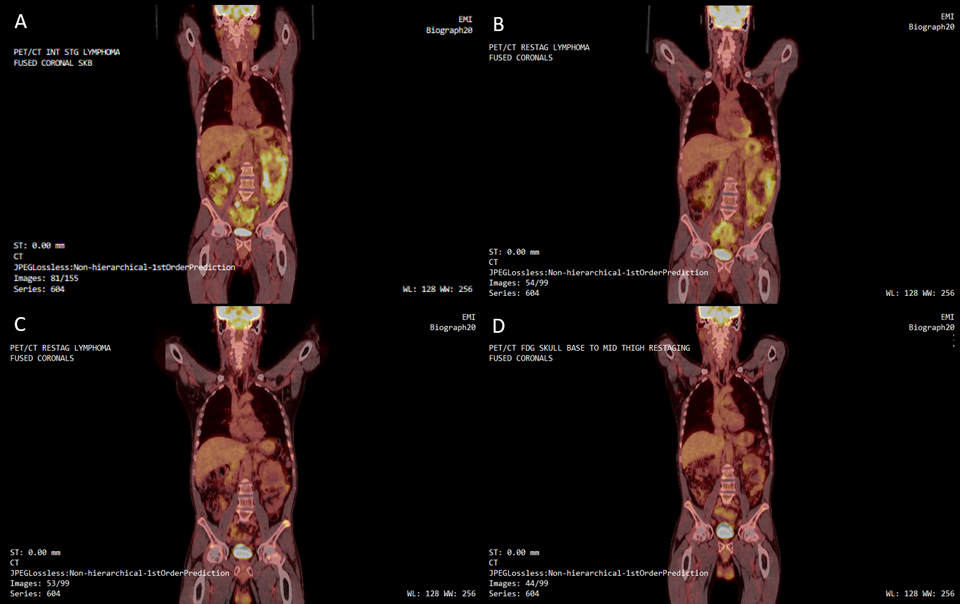

Fasting in the management of follicular Lymphoma

This preliminary study will begin to observe and quantify the effects of fasting on low-grade follicular lymphoma.